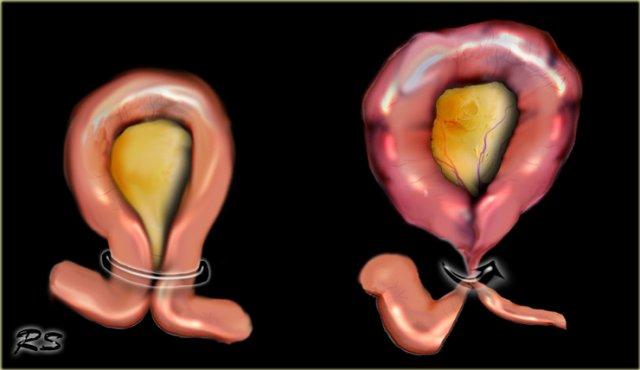

Tắc ruột dạng quai kín là một thể tắc ruột đặc biệt, trong đó hai điểm trên cùng một đoạn ruột bị tắc nghẽn tại một vị trí duy nhất, tạo thành một quai kín.

Nguyên nhân thường gặp là do dính ruột, xoắn mạc treo hoặc thoát vị nội.

Ở đại tràng, thể này được gọi là xoắn đại tràng (volvulus).

Ở ruột non, thể này đơn giản được gọi là tắc ruột non dạng quai kín.

Đặc biệt ở ruột non, nguy cơ thắt nghẹt và nhồi máu ruột rất cao với tỷ lệ tử vong từ 10-35%.

Xoắn Manh Tràng

Xoắn ruột luôn lan rộng ra xa khỏi vị trí xoắn.

Do đó, xoắn đại tràng sigma chỉ có thể di chuyển lên trên và thường đi về phía góc phần tư trên bên phải.

Ngược lại, xoắn manh tràng có thể di chuyển đến hầu hết mọi vị trí và thậm chí có thể nằm ở vùng chậu (hình minh họa).